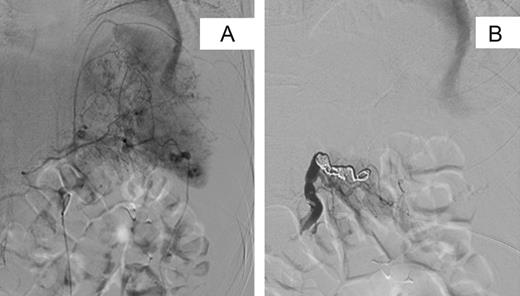

An urgent contrast-enhanced computed tomography (CECT) scan of head, neck, thorax, abdomen and pelvis was performed, demonstrating a Grade 4/5 splenic laceration with several foci of active haemorrhage and a large volume of peri-splenic free fluid consistent with blood with no other intra-abdominal injuries (Fig. 1). Following review, a decision was taken to perform angiography with a view to selective angio-embolization as the patient remained haemodynamically stable. Contrast angiography demonstrated multiple small pseudoaneurysms within the peripheral branches of the splenic artery with active contrast extravasation. The splenic artery was selectively catheterized and embolized at its mid-point with several coils (Fig. 2). At the end of the procedure, collaterals were seen supplying the residual non-injured splenic tissue, with the absence of active contrast extravasation. The patient was transferred to the intensive care unit for continuous haemodynamic monitoring for 36 h. Appropriate additional plain facial and long limb imaging was performed when stable, and no additional injuries were noted. She made an uneventful recovery and was discharged 9 days following admission. An abdominal ultrasound scan, 6 weeks later, confirmed almost complete resolution of the peri-splenic haematoma.

Selective digital subtraction angiography pre- and post-splenic artery embolization. (A) Pre-embolization image demonstrating multiple focal areas of haemorrhage. (B) Post-embolization image demonstrating coils within the main splenic artery with early filling of collateral vessels.